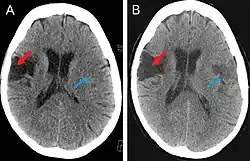

Scanning techniques include EEG, SPECT, MRI, and CT brain scanning.[1][2] These additional techniques are useful in determining what type of lesion the patient has, and allows physicians to determine more effective ways in treating the patient.

This computer-tomography type of imaging is one of the most used in any clinical environment and although it can detect some of the brain areas affected by a stroke or a trauma it does not provide the same acuity as the magnetic resonance imaging. CT scans can also reveal, in patients with the syndrome, the bilateral cortical infarcts located in the posterior frontal region involving the opercular areas.[3]